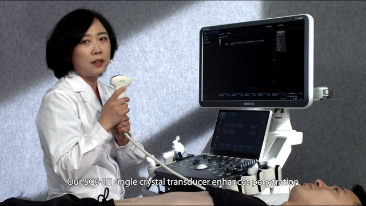

Resona 7

Gelombang Baru dalam Inovasi Ultrasound

Sejak didirikan, Mindray terus mencari cara baru untuk meningkatkan keandalan diagnostik. Didukung Teknologi ZONE Sonography? terkini, platform ZST+ baru Resona 7 meningkatkan kualitas gambar ultrasound melalui pengambilan zona dan pemrosesan data saluran.

Selain kualitas gambar premium, Resona 7 juga meningkatkan kemampuan penelitian klinis dengan V Flow revolusioner untuk evaluasi hemodinamika vaskular, serta pengambilan penampang tercanggih dari rangkaian data 3D untuk diagnosis CNS pada janin. Kombinasi pengoperasian multisentuh berbasis gerakan yang paling intuitif dengan semua fitur klinis penting membuat Resona 7 menjadi gebrakan baru dalam inovasi ultrasound.